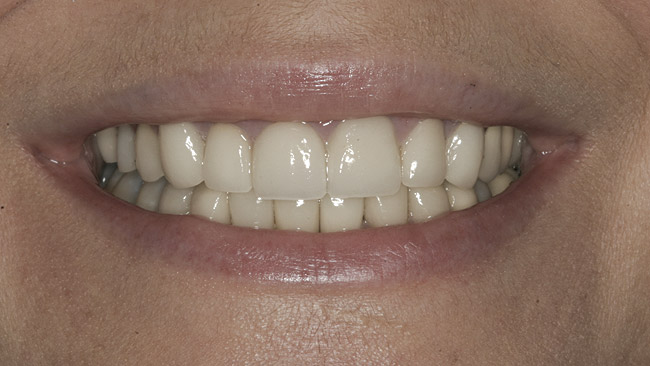

Figure 23  Final zirconia crown, No. 9—full-smile view.

Figure 23

The final screw-retained crown was delivered and torqued onto the implant to 35 Ncm; the restorative dentist then sealed the screw access with a cotton pellet and composite (Figure 20 and Figure 21). Various views of the final crown are shown in Figure 22 through Figure 25, including a full-face photograph.

The patient, who works as a professional model, was pleased with her esthetic result, which was a paramount criterion for the team approach applied to this case, as emphasized by Vermylen et al, who reported positive to very positive ratings on esthetics and phonetics among 48 patients with 52 implants on which crowns were fabricated by their restorative dentists.12

The gingival frame of the final implant crown on tooth No. 9 successfully matched that of natural tooth No. 8 (Figure 23). Accomplishing this required not only preservation of the existing free-margin height, but also the mirroring of the zenith point (at the approximate junction of the middle and distal thirds of each incisor’s clinical crown).